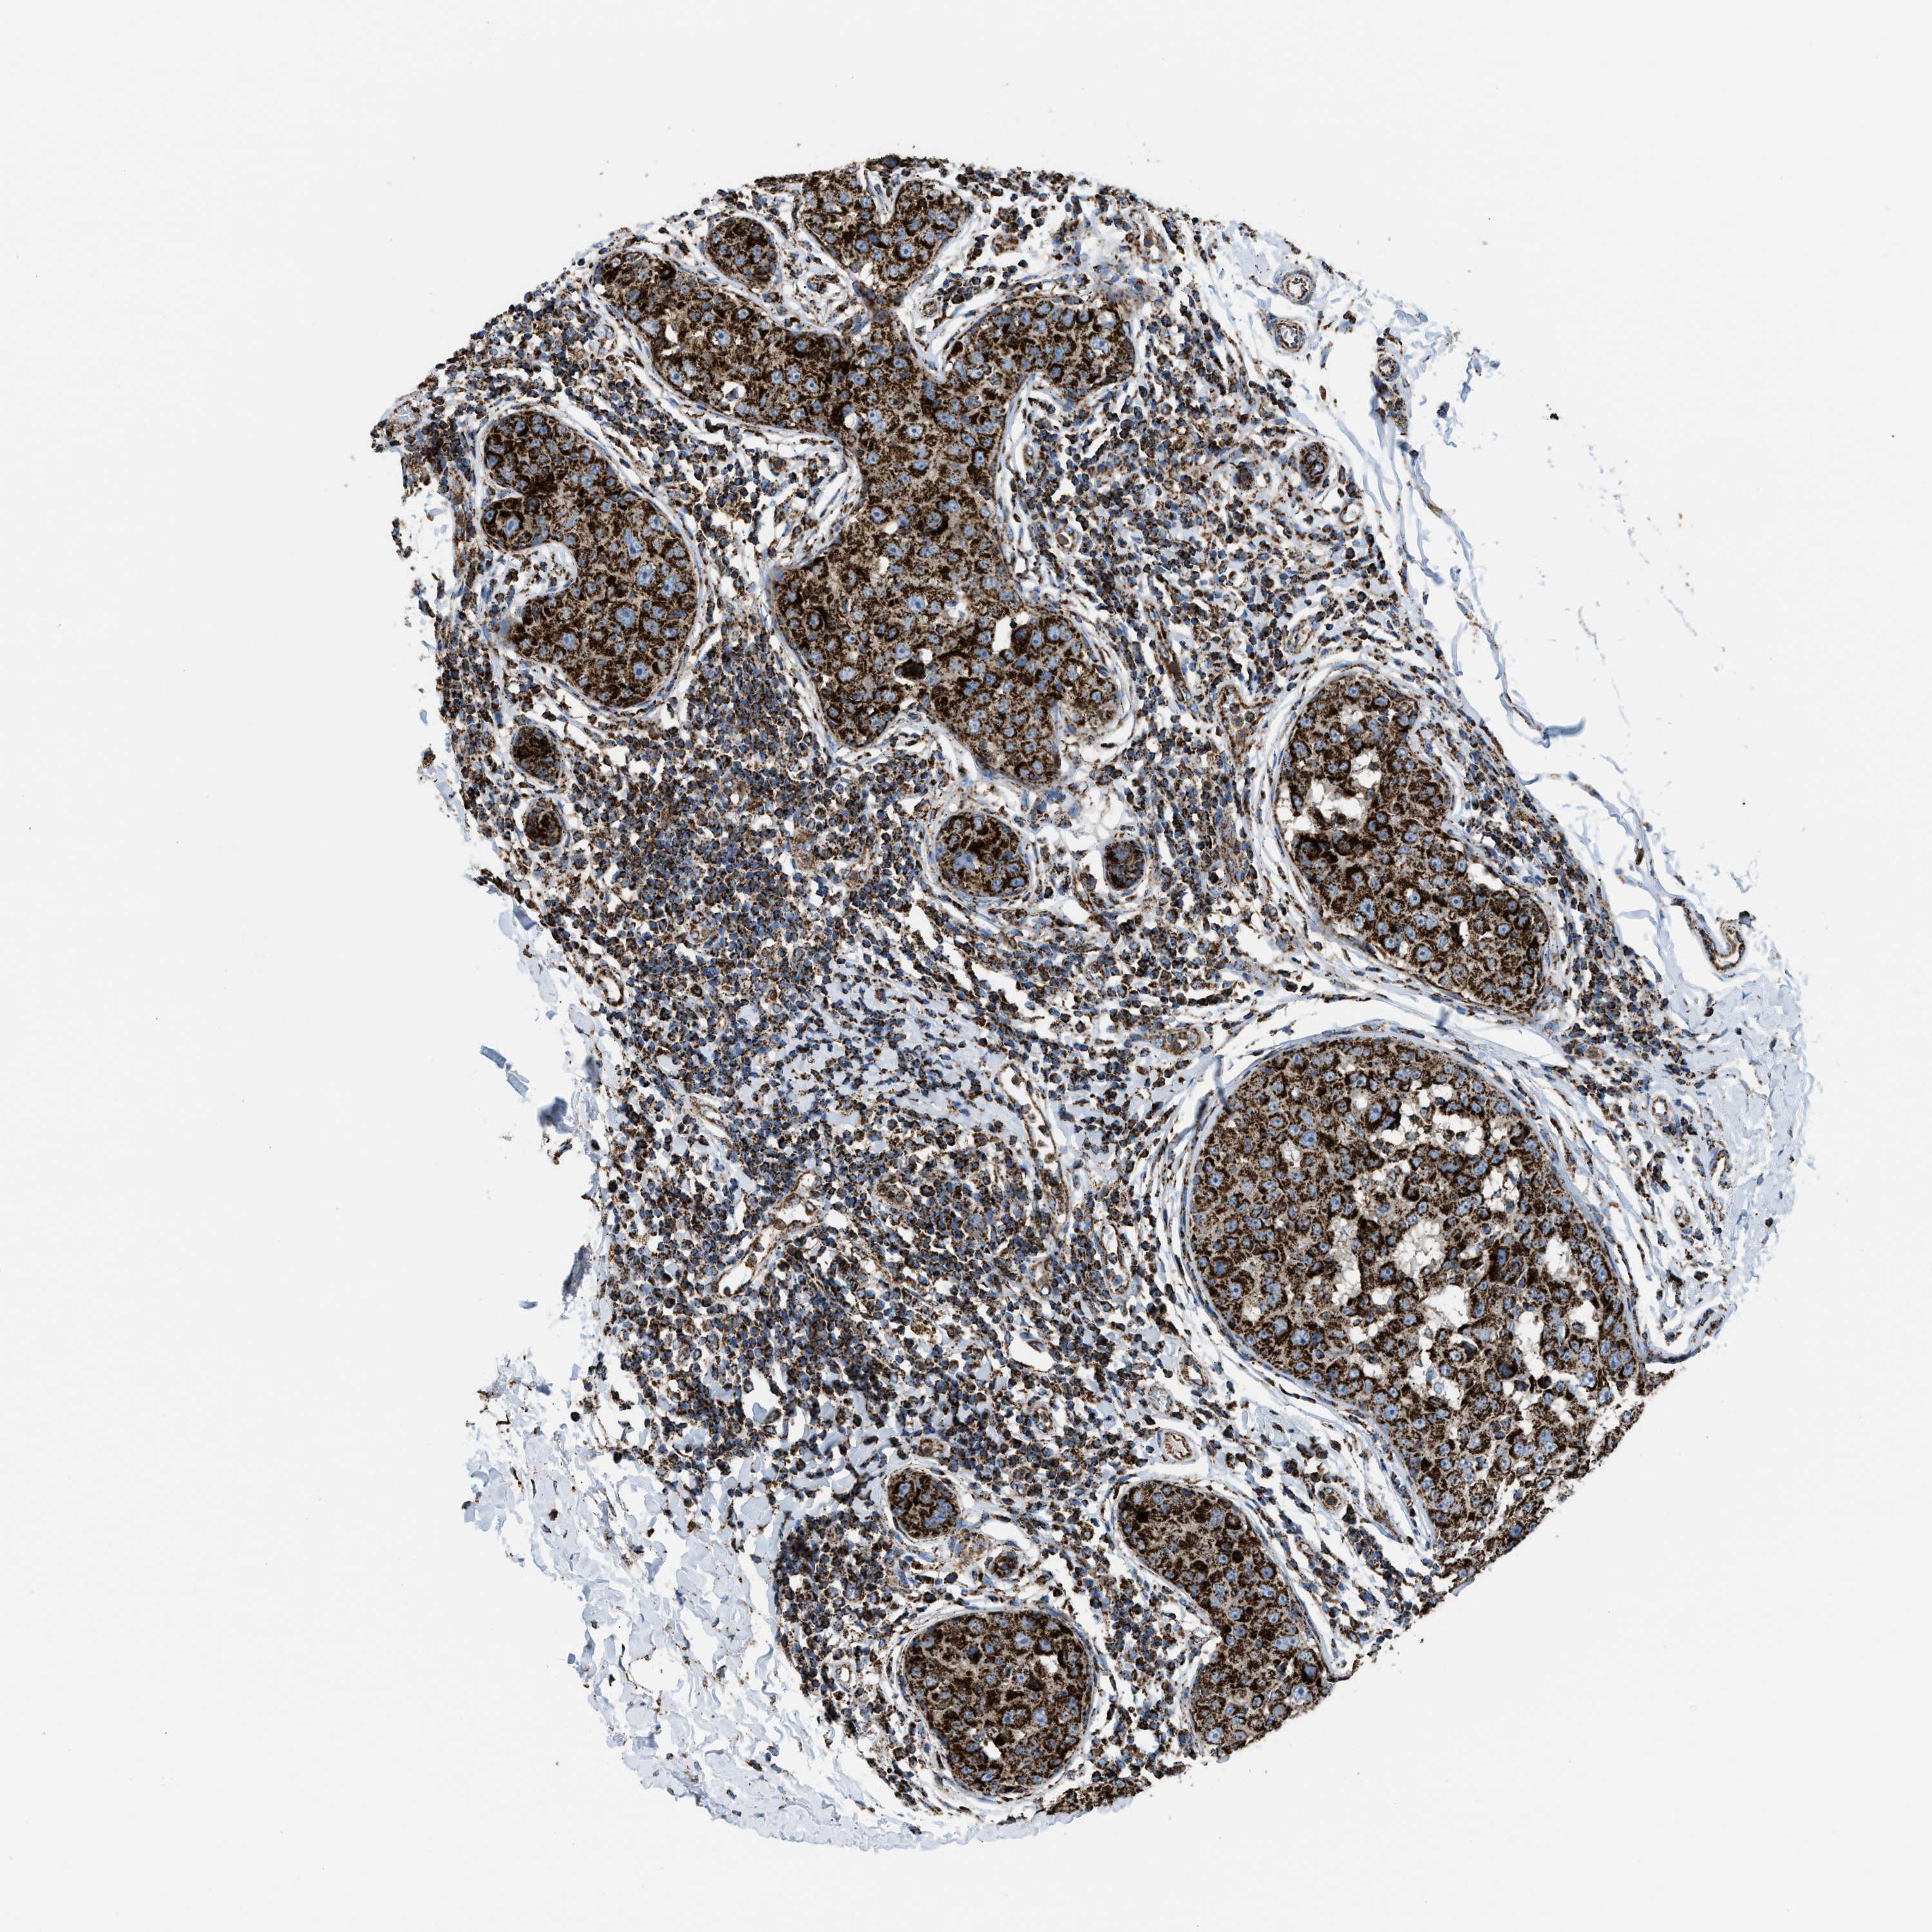

CANCER BREAST CANCER Show tissue menu

BRCA TCGA BRCA VALIDATION PROTEIN EXPRESSION